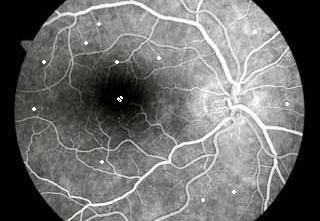

Μια αποκαλυπτική εξέταση για διάγνωση αλλοιώσεων απο σακχαρώδη διαβήτη, παθήσεων της ωχράς και άλλων παθήσεων του οφθαλμού. Γίνεται με την ενδοφλέβια χορήγηση μιας φθορίζουσας ουσίας που μας επιτρέπει , με μιά ειδική κάμερα να φωτογραφίσουμε τον βυθό του ματιού και την κυκλοφορια  μεσα στα αγγεία του  ματιού. Κατόπιν εαν χρειαστεί παρεμβαίνουμε με laser.